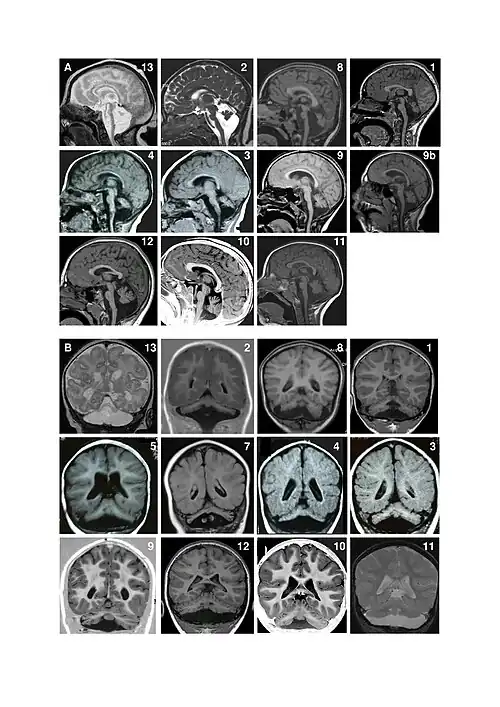

Pontocerebellar hypoplasia (PCH) is a heterogeneous group of rare neurodegenerative disorders caused by genetic mutations and characterised by progressive atrophy of various parts of the brain such as the cerebellum or brainstem (particularly the pons).[1] Where known, these disorders are inherited in an autosomal recessive fashion. There is no known cure for PCH.[2]